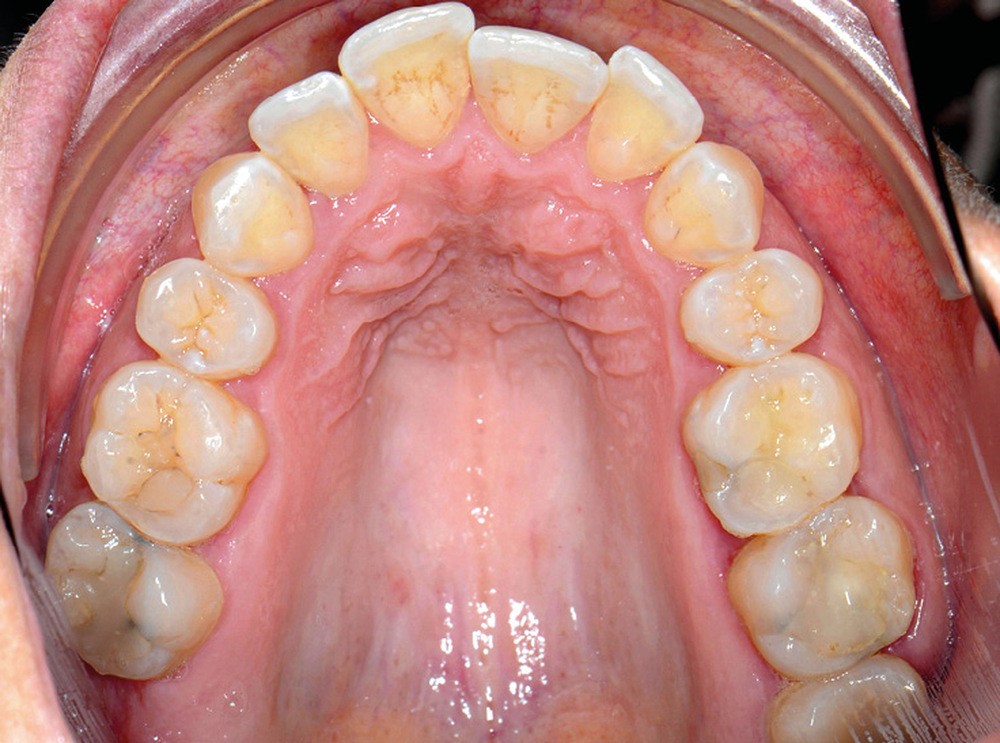

C’est précisément le cas de cette patiente de 33 ans qui présente une classe II squelettique par rétrognathie mandibulaire sur un schéma vertical hyperdivergent associée à une classe II/1 dentaire avec DDA par excès et biproalvéolie. Son profil est convexe, cis-frontal et, sur le plan fonctionnel, on peut observer une dysfonction linguale et une incompétence labiale au repos. Il en résulte une contracture des muscles de la sphère péri-orale lèvres jointes. La formule dentaire n’est pas complète puisque les quatre deuxièmes prémolaires ont été extraites lors d’un premier traitement orthodontique et qu’il y a également agénésie des troisièmes molaires 18 et 38 (fig 1 à 11).